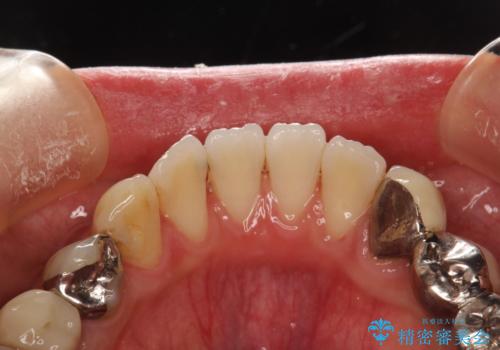

治療のスタート前に着色・ステインをPMTCできれいに除去

- 今まで歯科医院でのクリーニングを受けたことがないとの事でした。これから、虫歯治療が開始されるため、まずは全体的にクリーニングを希望されました。PMTC60分コースを行いました。

歯の表面に、茶色く色が残っている所がありますが、これは詰め物の変色の所と、虫歯になっている所です。以前に、CR(コンポジットレジン)による虫歯治療がされています。

CRは経年的劣化や、着色してしまうことがあります。PMTCでクリーニングを行うと、古いCRが目立つことがあるため、気になる際は詰め替えを行います。

茶色くなっている部分が、着色なのか、劣化なのか、虫歯によるものなのかは判別が難しいことがあります。そのため、定期的にPMTCを行うことで状態の確認が的確に行えます。

また、治療が開始される前などにも、全体的にクリーニングを行いご自身本来の歯の色、状態を精密に確認することが大切です。